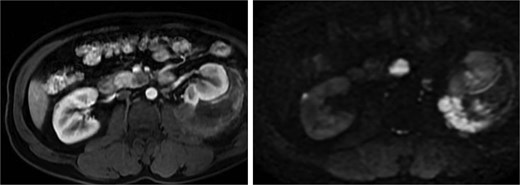

A pancreatic uncinate process mass measured 18 × 20 mm and was hypointense on T1-weighted and mildly hyperintense on T2-weighted imaging, with relative hypoenhancement compared with adjacent pancreatic parenchyma and marked diffusion restriction (Fig. 5). A right adrenal mass measured 12 × 16 mm, was mildly hyperintense on T2-weighted imaging, and showed contrast enhancement and diffusion restriction (Fig. 6). Brain MRI demonstrated no intracranial lesions.

MRI of the pancreatic uncinate process mass showing low T1 signal, mildly increased T2 signal, restricted diffusion, and relative hypoenhancement on post-contrast images.

MRI of the right adrenal lesion showing mild T2 hyperintensity, contrast enhancement, and restricted diffusion.